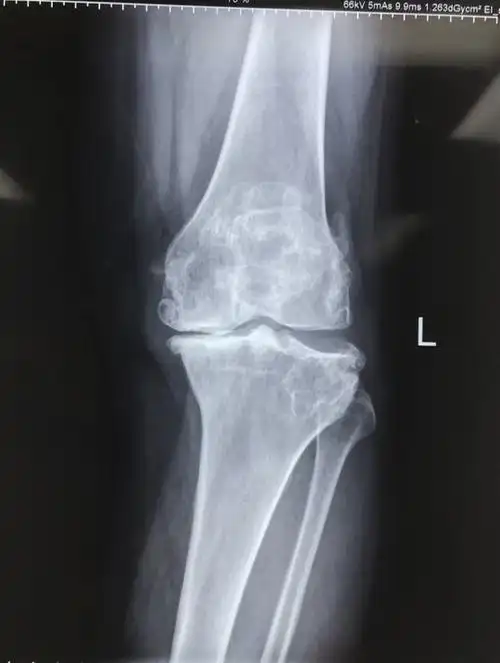

8 膝内翻x片.jpg

7膝内翻全长片.jpg